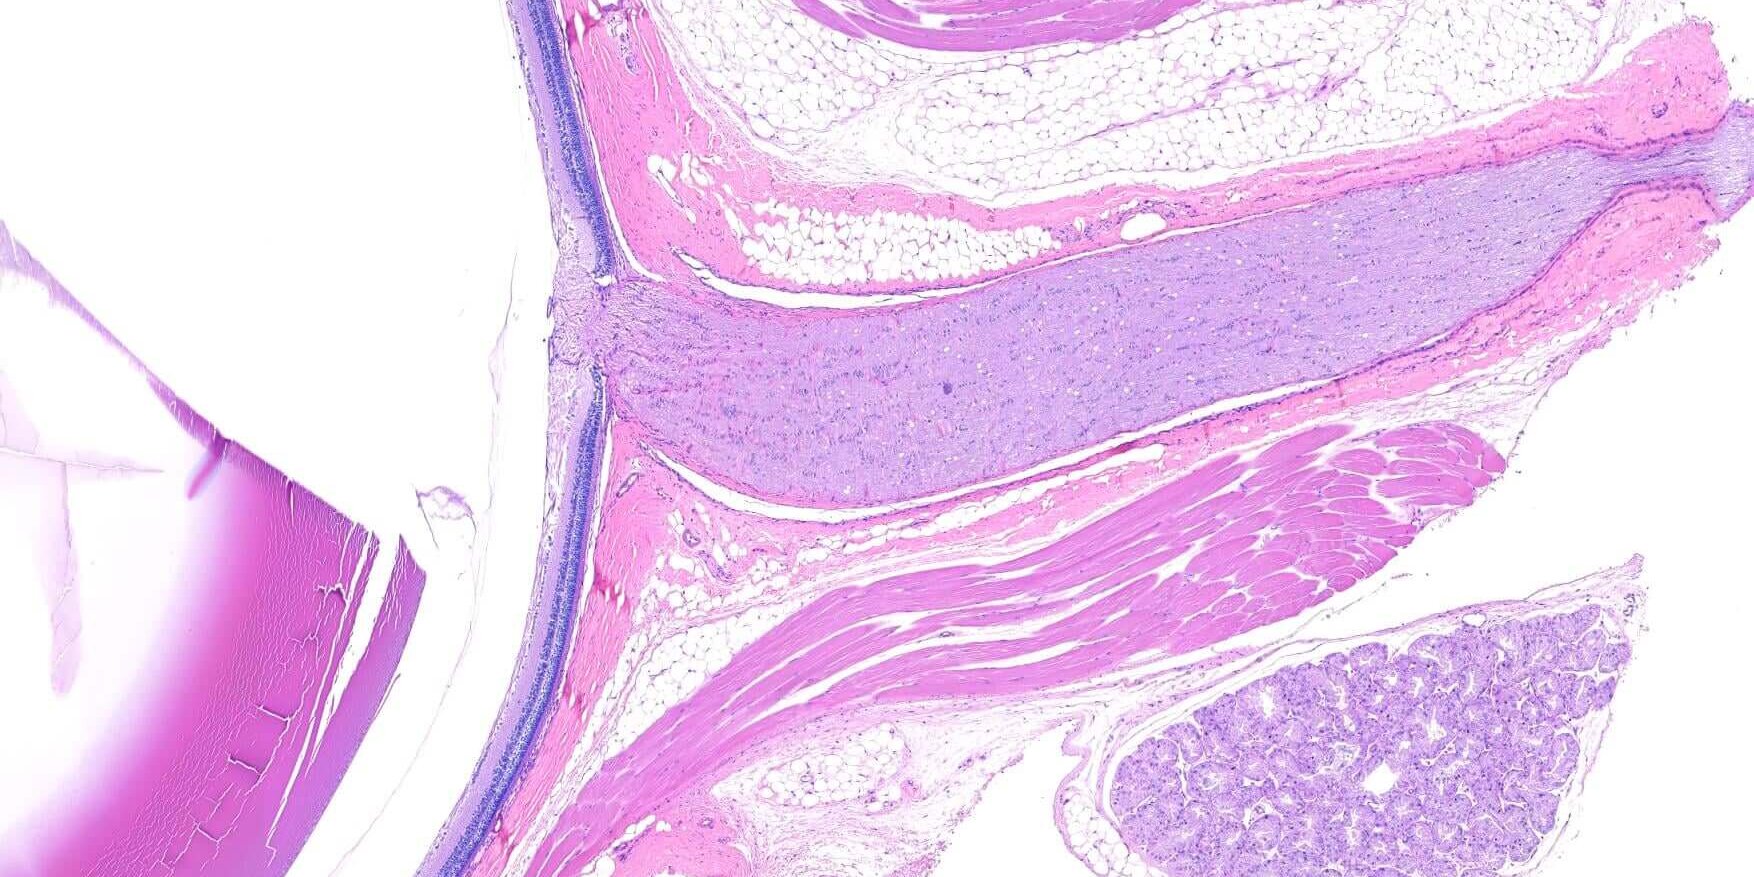

9 月272021最新消息立眾病理 立众病理實驗室一向將病理切片技術視為一門藝術,追求極致的工藝技術,展現精益求精的匠人精神 ! 一個完美的眼球組織切片,需要有純熟的採樣技術、正確的固定液選用、準確的組織修整定位及頂尖的切片技術。立众病理實驗室十年磨一劍,透過經驗的積累、傳承,並與客戶耐心的溝通討論,才能取得如此精美的眼球組織切片!! Post navigationPreviousPrevious post:IHC可見光雙重染色 – 藝術品般的染色表現NextNext post:立众生技獨家代理BioTnA染色試劑套組Related Posts本公司病理獸醫師主任張皓凱,獲邀至2026年中華民國獸醫病理學會之會員大會進行專題演講2026-03-18犬口腔T細胞淋巴瘤 (T cell lymphoma)2022-07-22Picro-Sirius red 天狼星紅染色2022-07-22皮膚專科的病理診斷服務來囉!2022-07-22Modified Movat’s Pentachrome 染色法2022-07-22植物也能做組織切片!!?2022-03-23